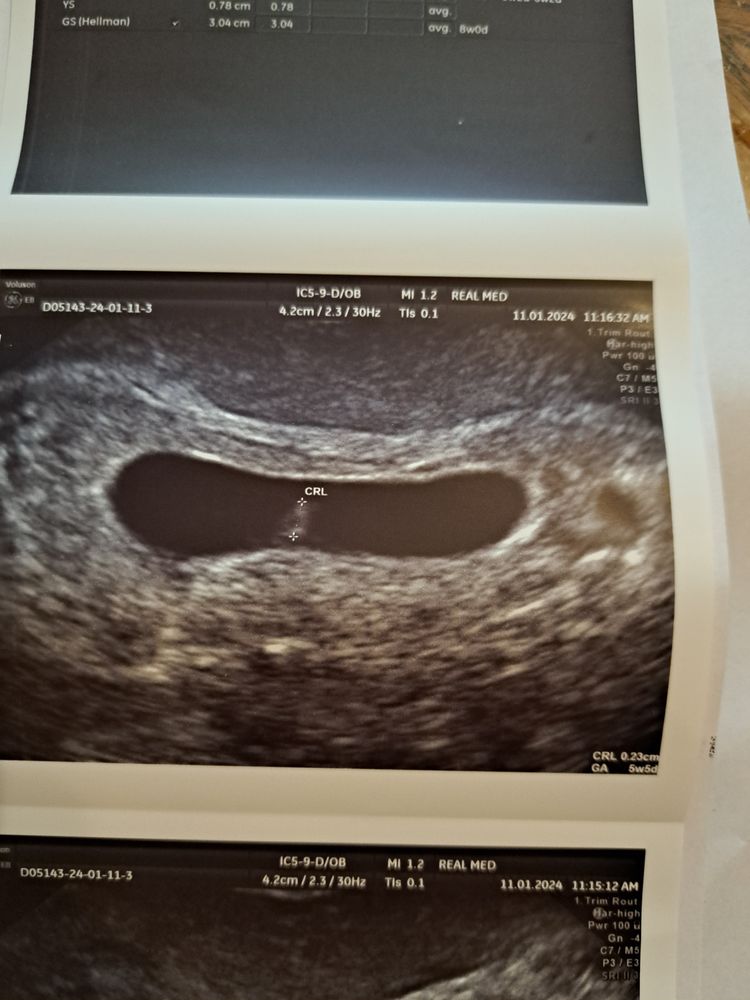

Пошла на узи. Эмбриончик на 5 недель, по месячным 7 недель 4 дня, сердцебиение отсутствует. Огромный желточный мешочек. Грусть, печаль😭

Эмбрион на 5 нед 5 дней

Желточный мешочек 7.8 мм больше нормы этого срока в 2 раза

Плодное яйцо на 8 недель по размерам